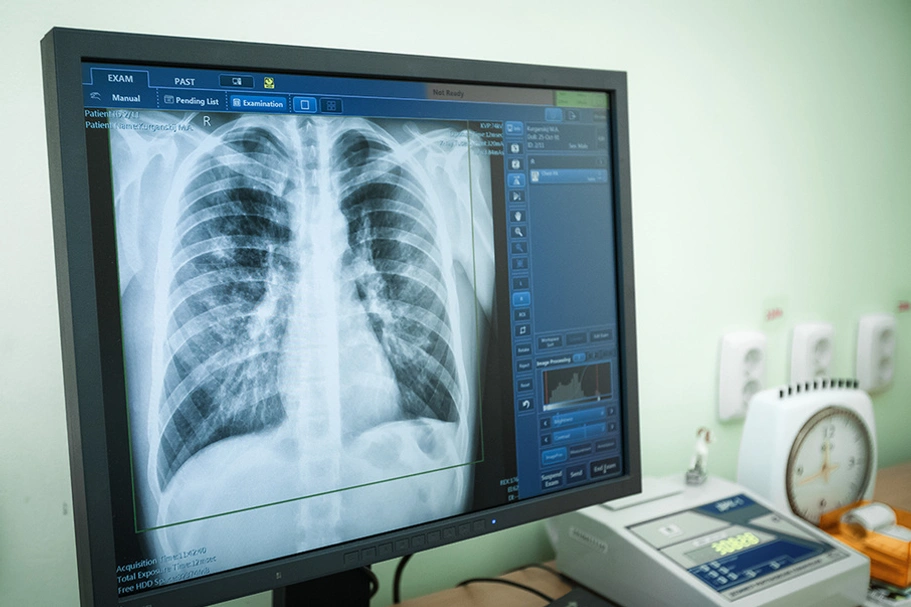

В России ведется подготовка к переходу на новый порядок массовой диагностики туберкулеза у несовершеннолетних. По новым правилам, кроме пробы Манту, будет применяться диаскинтест, об этом сообщила пресс-служба ведомства. Приказом Минздрава РФ от 21.03.2017 №124н «Об утверждении порядка и сроков проведения профилактических осмотров граждан в целях выявления туберкулеза» определяется применение для диагностики туберкулеза не только пробы Манту и флюорографии, но и диаскинтеста. Детям до 7 лет будет делаться проба Манту, для диагностики туберкулеза у детей с 8 до 17 лет (включительно) будет применяться диаскинтест.

– Для массового обследования детского населения в целях выявления туберкулеза будут использоваться кожные пробы с аллергенами туберкулезными (аллерген туберкулезный очищенный в стандартном разведении – детям от 1 до 7 лет (включительно), аллерген туберкулезный рекомбинантный в стандартном разведении – детям от 8 до 14 лет (включительно), а для детей в возрасте от 15 до 17 лет (включительно) – аллерген туберкулезный рекомбинантный в стандартном разведении) или рентгенологическое флюорографическое исследование органов грудной клетки (легких), – приводит документ РИА АМИ.

Приказ вступит в силу после отмены старого документа, который действовал с 2001 года. Новый приказ разработан совместно с профессиональным медицинским сообществом.